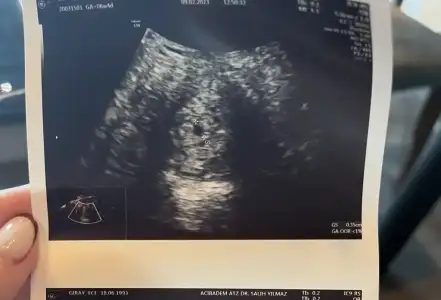

Belki takip etmişsindir benim değerlerim çok saçma arttı. Tam bitti dedik 2 katı oldu birden. Doktorumun dediği başta 2 embriyo da tuttu ama yola biri devam ediyor. Salı gittiğimde bişey yoktu. Perşembe beta artınca gittim kese daha yeni oluşmuş 2-3 mm dedi. Haftaya perşembe bir daha gidicem en azından kese büyüyor mu içinde yolc sac var mı bakalım dedi

Evet evet yazılarınızı okudum hep. Olsun 1 tane olsun sağlıklı olsun sizin olsun 🥰 aa sizin keseniz yeni oluşuyor. Bana doktor dedi yolk keseside görünüyo gibi dedi ama çok arafta konuştu doktor her konuda sevemedim başka bi doktora gidicem ilerleyen zamanda. Masus kaç haftalık diye sordum. 5 gibi duruyo dedi. Net bişey diyemedi. Ama telefondaki programda 5+2 çıkıyo. 5 gibi duruyo ne demek. 🙄

Benim değerim 2 gün 830 ve 860’ta kaldı sonra 1600’e çıkınca geç oluştu. Baktım sizinkinde 7.5 benimkinde 5 yazıyor geriden geliyorum 😂 umarım benimkinde bir sıkıntı çıkmaz çok korkuyorum aksilik yaşadığım için. İçinize sinen hep ulaşabileceğin bir dr bul🙏🏻

Naz yapıyo size annecisi 🥰🥰 kese görünmüş ya sağlıkla ilerler inşallah ❤️ 7.5 şuan siz diyince farkettim desem 😂 ben hep sağ alt köşeye bakıyordum 😅

Teşekkür ederim 😍 Rabbim herkesiin gönlüne göre versin. Ben 8. Ve 10. Günü kan testi verdim sonra 8 gün bekledm öyle gittim doktora. Doktor hesapladı muhtemelen betan 3000 i geçmiştir kesen görünür dedi. Benim 10. Gün 400 dü